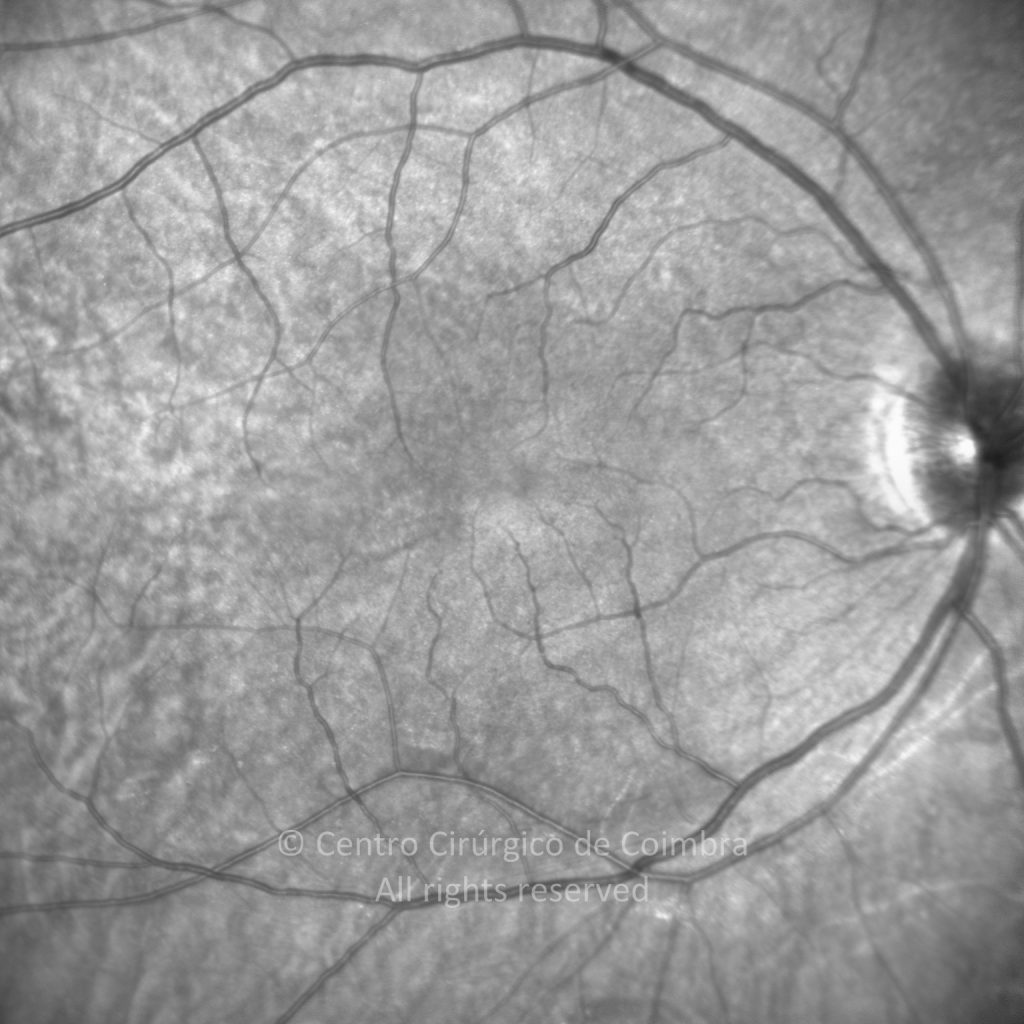

Paciente de 37 años con traumatismo contundente y ruptura del globo ocular. Presenta ruptura esclero-uveal, hifema, hemovítreo, desgarro periférico y temporal de la retina, hemorragias subretinianas y múltiples desprendimientos serosos.

MAVC: 20/25 OD, nueve años después de las cirugías (sutura escleral de la desinserción del músculo recto externo, vitrectomía posterior y fotocoagulación láser en el borde del desgarro retiniano, desprendimiento de retina inferior con proliferación vitreorretiniana y líquido subretiniano con algo de sangre; peeling de la membrana epirretiniana y maculorrexis de la MLI).